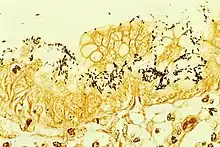

Micrograph of H. pylori colonizing the stomach lining

H. pylori colonized on the surface of regenerative epithelium (Warthin-Starry silver stain)